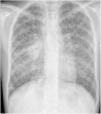

L. was diagnosed with Crohn's disease at the age of 7. She was first treated with oral corticosteroids for 9 months, then azathioprine. Because of persistent symptoms, anti-tumor necrosis factor agents (first infliximab during 3 years, and then adalimumab for 6 months) were added to azathioprine. The child had received BCG vaccination when aged 2 months. The tuberculin skin test was negative, and IGRAs (interferon gamma release assays=QuantiFERON-TB-Gold Cellestis) results were indeterminate before starting anti TNF agents. Abdominal pain, diarrhea, with evening rise fever were persistent despite anti TNF agents. One month after adalimumab was dropped when the child was eleven; ustekinumab treatment was started together with azathioprine, after a collective decision of pediatric and adult gastroenterologists (Fig. 1). No chest X-ray was performed before starting ustekinumab. It was started after 15 days of oral corticosteroids (budesonide 9mg per day). Fifteen days after the first injection of ustekinumab (6mg/kg intravenously), she was referred to our pediatric pulmonology unit for persistent fever, dry cough and weight loss. On clinical examination: oxygen pulse oximetry: 97% (room air); temperature: 39°C; no tachypnea or retraction signs; auscultation showed crackles in the right inferior lobe. Chest X-ray (Fig. 2) showed diffuse alveolo-interstitial opacities, with right parahilar consolidation with central cavitation that is over the helium of 51mm×36mm, and nodules with diffuse distribution of 2–4mm. Blood test showed moderate inflammation (C-reactive protein 80mg/l). Viral and bacterial nasopharyngeal aspirates were negative (Mycoplasma and Chlamydia pneumoniae, multiplex viral PCR). Fiberoptic bronchoscopy showed obstruction of the apical bronchi of the right inferior lobe by endobronchial granuloma. Broncho alveolar lavage showed normal cellularity, with lymphocytosis (=135cells/mm3, with 33% macrophages, 51% lymphocytes, 16% neutrophils). Bacterial culture was negative, as well as respiratory viruses and mycology culture (Pneumocystis jirovecii) on BAL. Acid fast bacilli (AFB) was detected by microscopy using Ziehl Neelsen stain on BAL, sputum smear and post bronchoscopy gastric aspirate. Culture grew for multisensible Mycobacterium tuberculosis. At that time, tuberculin skin test was negative, and IGRA (QuantiFERON-TB-Gold Cellestis) was indeterminate. There were no close contacts with tuberculosis. Thoracic computed tomodensitometry (Fig. 3) was consistent with disseminated tuberculosis. In both lungs there are multiple nodules being the largest in the superior segment of the right lobe where there are bigger than those located in other lobes; multiple adenopathy in the right hilar and interlobar regions; and condensation of 35mm×26mm of the apical segment of the right inferior lobe, with two central excavation of 12mm×5mm and 10mm×7mm.

Because of disseminated tuberculosis, a search for multiorgan involvement was carried out: urinary culture was negative; abdominorenal echography, echocardiography, bone scintigraphy, ophthalmoscopic examination were normal. Cerebral MRI showed punctiform enhancement consistent with a right and left cerebellous granuloma, lumbar puncture was sterile, and neurological examination was normal with no cerebellous syndrom. Tuberculosis treatment was started with 2 months of quadritherapy: isoniazid–rifampicin–ethambutol and pyrazinamide, followed by 10 months of isoniazid and rifampicin (because of cerebral involvement). Azathioprine was temporarily suspended. The young patient was treated with corticosteroids (prednisolone 1mg/kg/day 15 days, with progressive weaning) in prevention of immune reconstitution inflammatory syndrome, and because of bronchial obstruction. Enteral nutrition was added because of undernourishment. On follow up, apyrexia was prolonged, the cough disappeared and the patient gained weight. Chest X-ray after 1 month of treatment was back to normal.

This is the first case described of disseminated TB in a child under ustekinumab for Chron's disease. Disseminated TB in this child was suspected on chest X-ray (and CT scan) and confirmed by the presence of Mycobacterium tuberculosis on sputum smear, BAL, and post FB gastric aspirate.

Typical chest radiograph findings may not be obvious until late in the disease. Typical findings on chest X-ray are collections of tiny discrete pulmonary opacities that are generally uniform in size and widespread in distribution, each of them measuring 2mm or less in diameter. In 10% of cases, nodules can be wider than 3mm in diameter, as in this case.